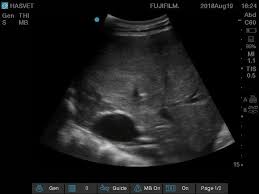

Kedi, köpek, tavşan, at ve çiftlik hayvanları için özel programlanmış Ultrason ile gebelik ve organ/sistem muayenelerini kliniğimizde yaptırabilirsiniz.

Ultrasonografi, yumuşak doku ve parankimal organların incelenmesinde, ses dalgalarından yararlanılan bir görüntüleme yöntemidir. Ultrasonografide, yüksek frekanslı ses dalgaları incelenecek bölgeye gönderilir ve bu dalgalar yansıtıcı bir yüzeye rastlayana kadar ilerler.